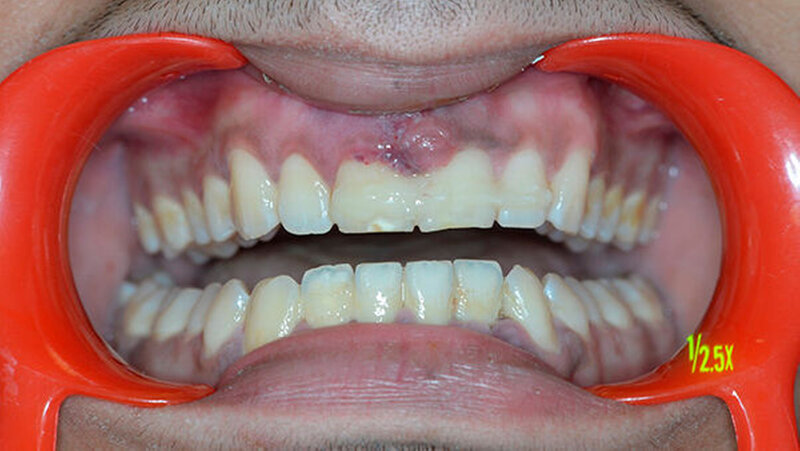

Der Zahn wurde zwei Stunden nach dem Unfall vital replantiert und semipermanent geschient. Die anschließende Abdrucknahme erfolgte unter allergrößter Sorgfalt. Die laborgefertigte Tiefziehschiene schließt die Bereiche der semipermanenten Schiene bis zum Schienenäquator mit ein. Was die Reanastomosierung der Gefäße und Nerven betrifft, ist der Behandler zuversichtlich, reagieren doch auch vital transplantierte Weisheitszähne nach einigen Wochen wieder auf Kältereize.